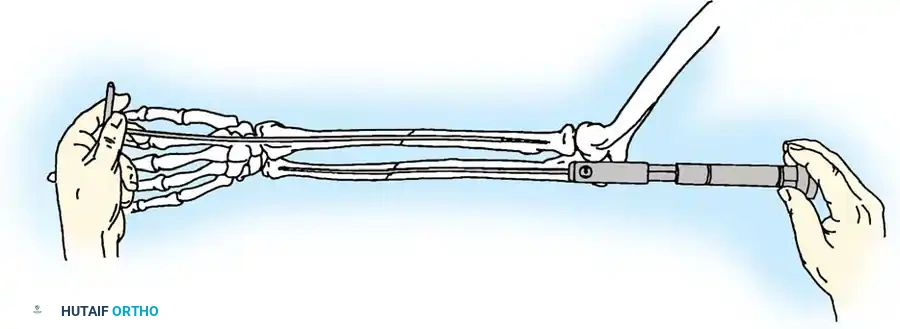

2. Intramedullary Fixation with Tension Band

If the fracture is more distal, or if there is a tendency for the proximal fragment to angulate posteriorly, a simple tension band wire is insufficiently stable. In these cases, intramedullary fixation (using Kirschner wires or a large cancellous screw) is combined with the tension band.

Kirschner Wires vs. Cancellous Screws:

* K-wires: The AO technique utilizes two parallel K-wires (1.6 mm or 2.0 mm) driven down the medullary canal. To prevent proximal migration, the K-wires must engage the anterior cortex of the ulna distal to the coronoid.

* Cancellous Screw: A biomechanical analysis by Murphy et al. demonstrated that a long 6.5-mm or 7.3-mm AO cancellous screw combined with a figure-of-eight wire provides a significantly stronger construct than K-wires. The screw must be long enough to achieve secure purchase in the ulnar diaphysis.

Fig. 54-55 Olecranon fracture repaired with long 6.5-mm AO cancellous screw and figure-of-eight tension band wire loop. Screw must engage cortex of diaphysis of ulna.